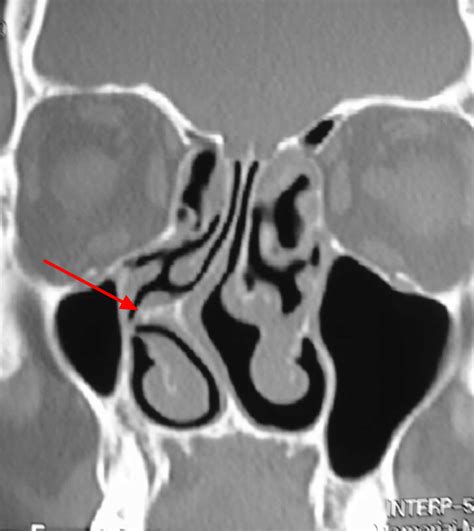

The nasal septum is the thin wall of bone and cartilage that separates your two nostrils. In an ideal anatomy, this wall sits directly in the center, creating two equal-sized air passages. However, it is quite common for the septum to be "off-center" or crooked. This is what medical professionals call a deviated nasal septum. When the deviation is significant, it can physically block one side of the nose and reduce airflow, leading to a variety of uncomfortable symptoms.